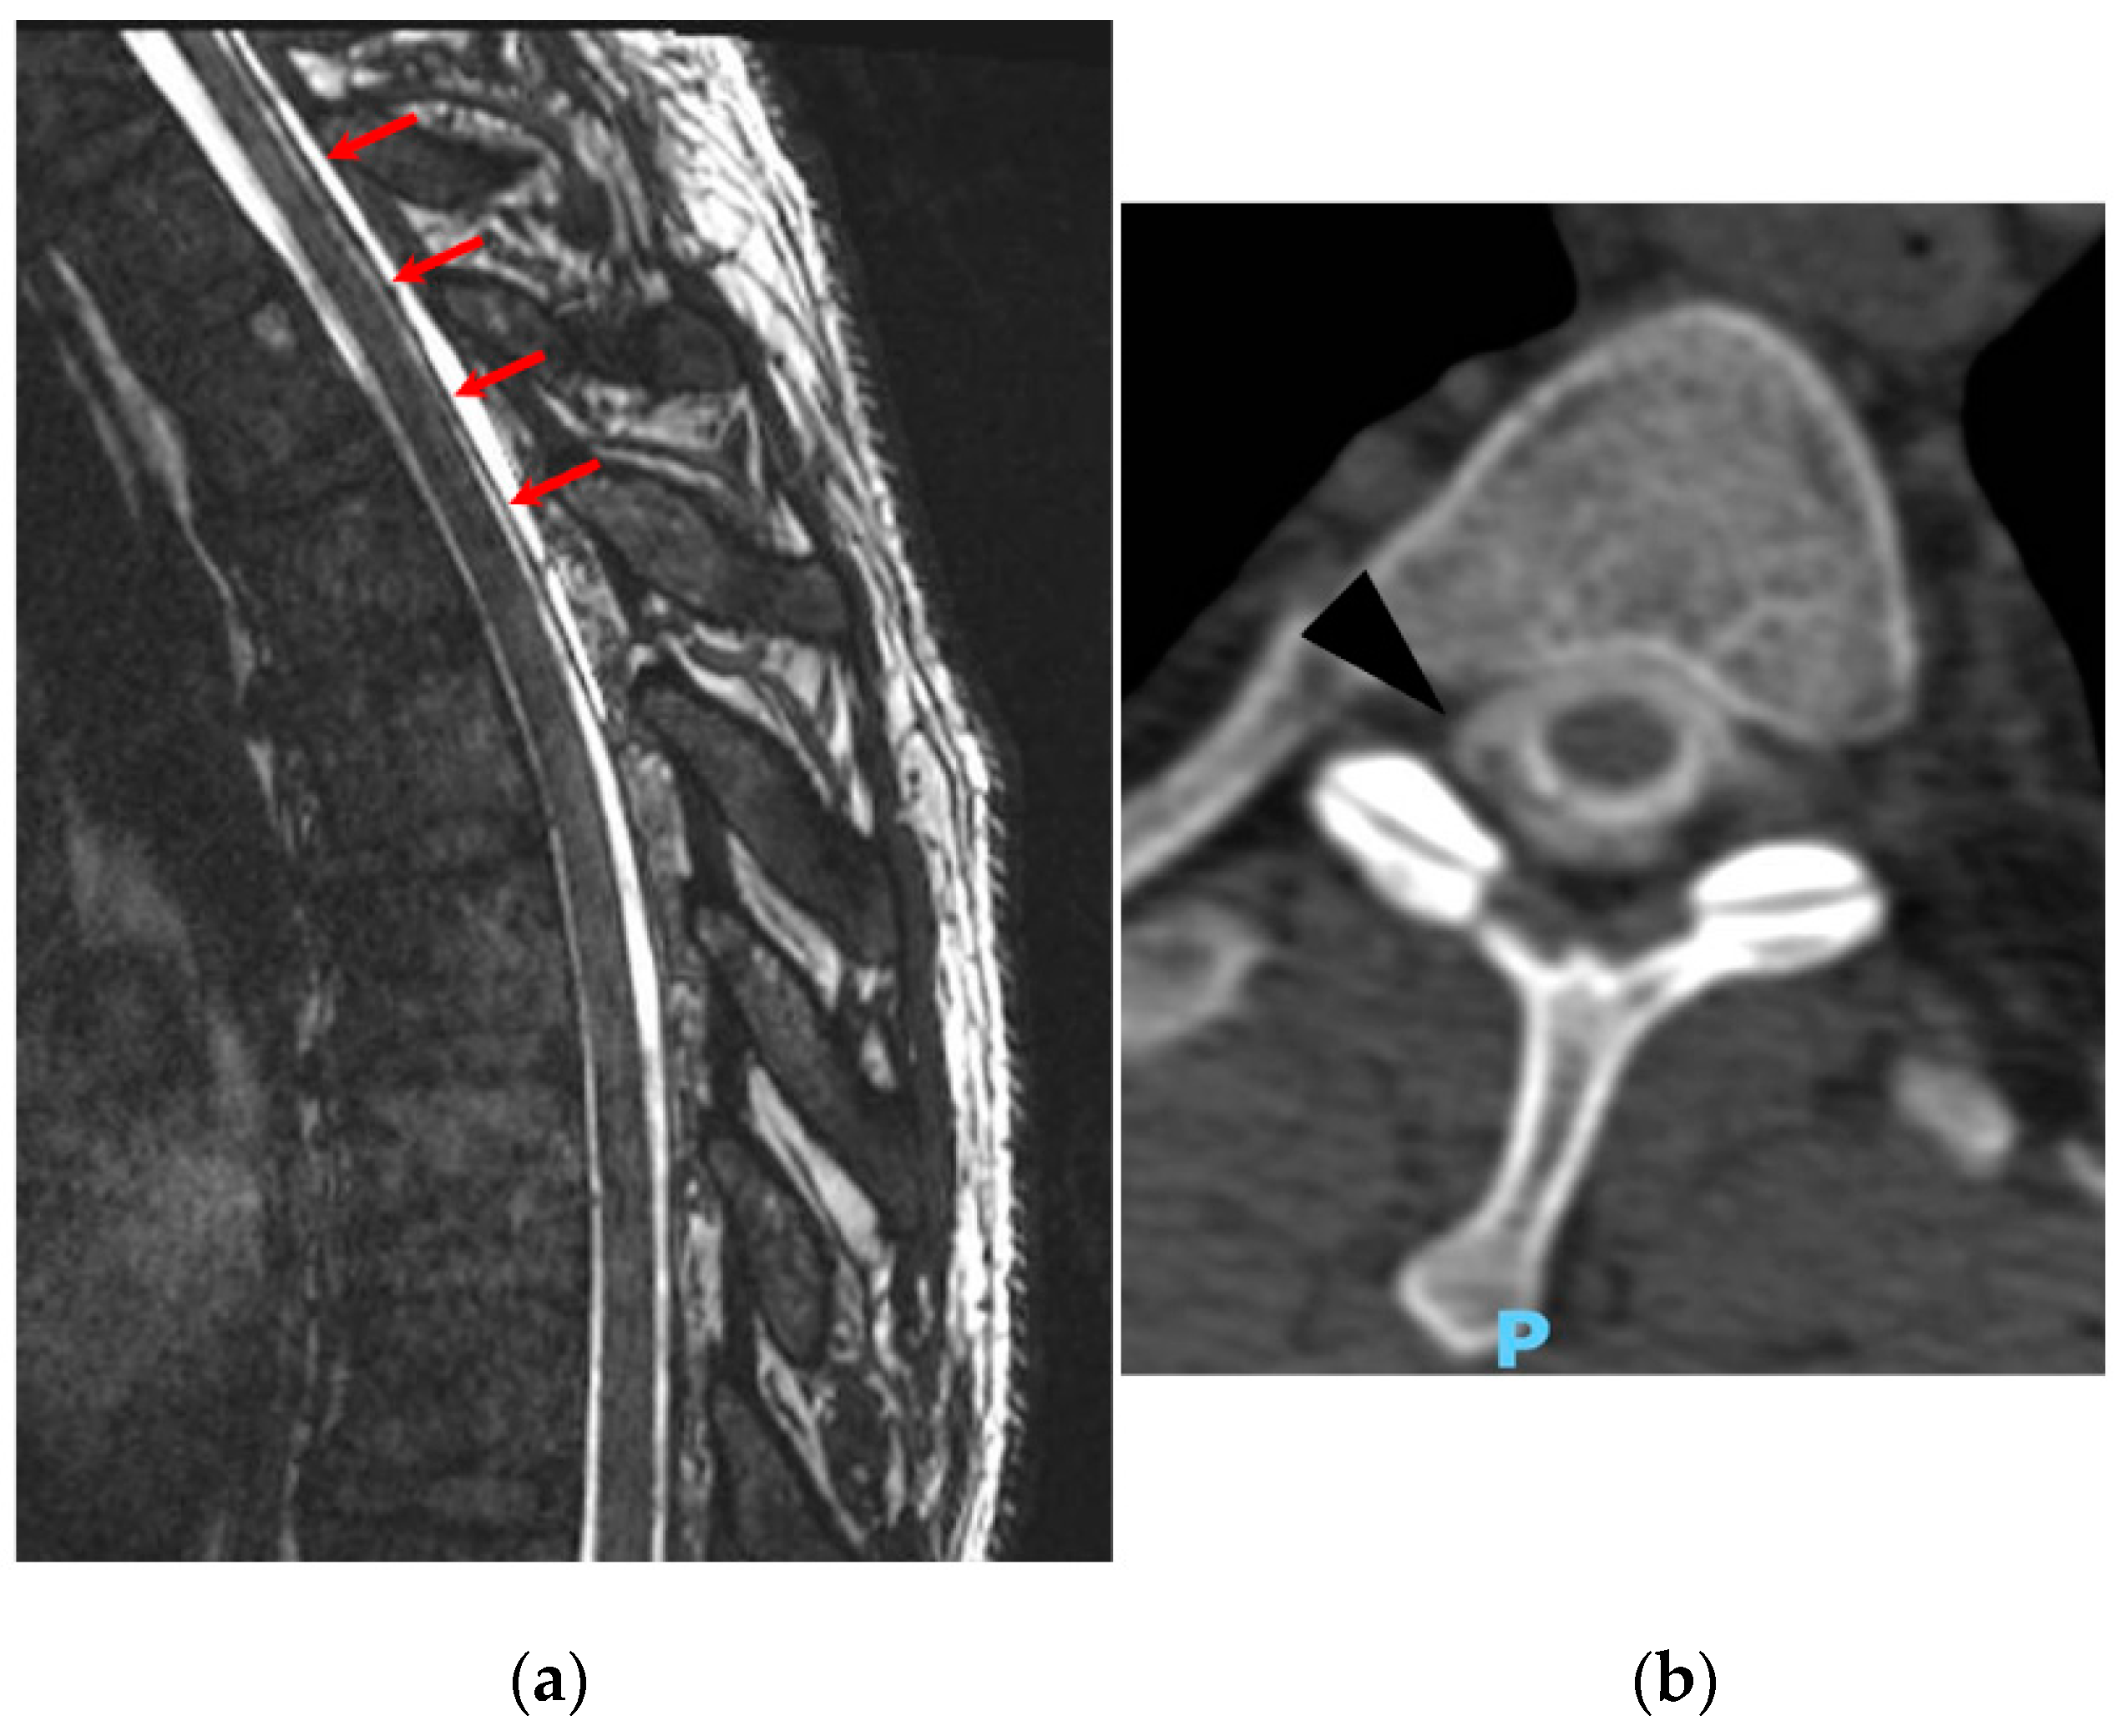

2. Case Report